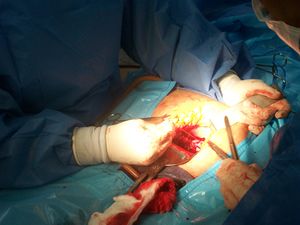

فريق طبي يجري عملية ولادة قيصرية.[1]  | |

الولادة القيصرية (إنگليزية: Caesarean section)، هي عملية جراحية يتم فيها شق بطن الأم لولادة طفل أو أكثر، وغالباً ما تُجرى لأن الولادة المهبلية قد تعرض الطفل أو الأم للخطر.[2] تشمل أسباب اللجوء للولادة القيصرية الولادة المتعسرة، الحمل بتوأم، ارتفاع ضغط الدم عند الأم، الولادة المقعدية، ومشاكل في المشيمة أو الحبل السري.[2][3] تُجرى الولادة القيصرية بناءً على شكل حوض الأم أو تاريخ الولادة القيصرية السابقة.[2][3] من الممكن أن تلد الأم ولادة مهبلية بعد الولادة القيصرية.[2] توصي منظمة الصحة العالمية بإجراء العملية القيصرية فقط عند الضرورة الطبية.[3][4] تُجرى بعض الولادات القيصرية بدون سبب طبي، عند الطلب من قبل شخص ما، عادة الأم.[2]

تستغرق الولادة القيصرية من 45 دقيقة إلى ساعة.[2] يمكن إجراؤها باستخدام التخدير النخاعي، حيث تكون المرأة مستيقظة، أو تحت التخدير العام.[2] تستخدم القسطرة البولية لتصريف المثانة، ثم يُنظف جلد البطن باستخدام مطهر.[2] عادة ما يُجرى شق بطول 15 سم تقريباً أسفل بطن الأم. [2] ثم يُفتح الرحم بشق ثانٍ ثم يُولد الطفل.[2] ثم تُغلق الشقوق بالمخيط.[2] عادة يمكن للمرأة البدء في إرضاع وليدها بمجرد خروجها من غرفة العمليات والإفاقة.[5] في كثير من الأحيان، يلزم قضاء عدة أيام في المستشفى للتعافي بشكل كافٍ قبل العودة إلى المنزل.[2]